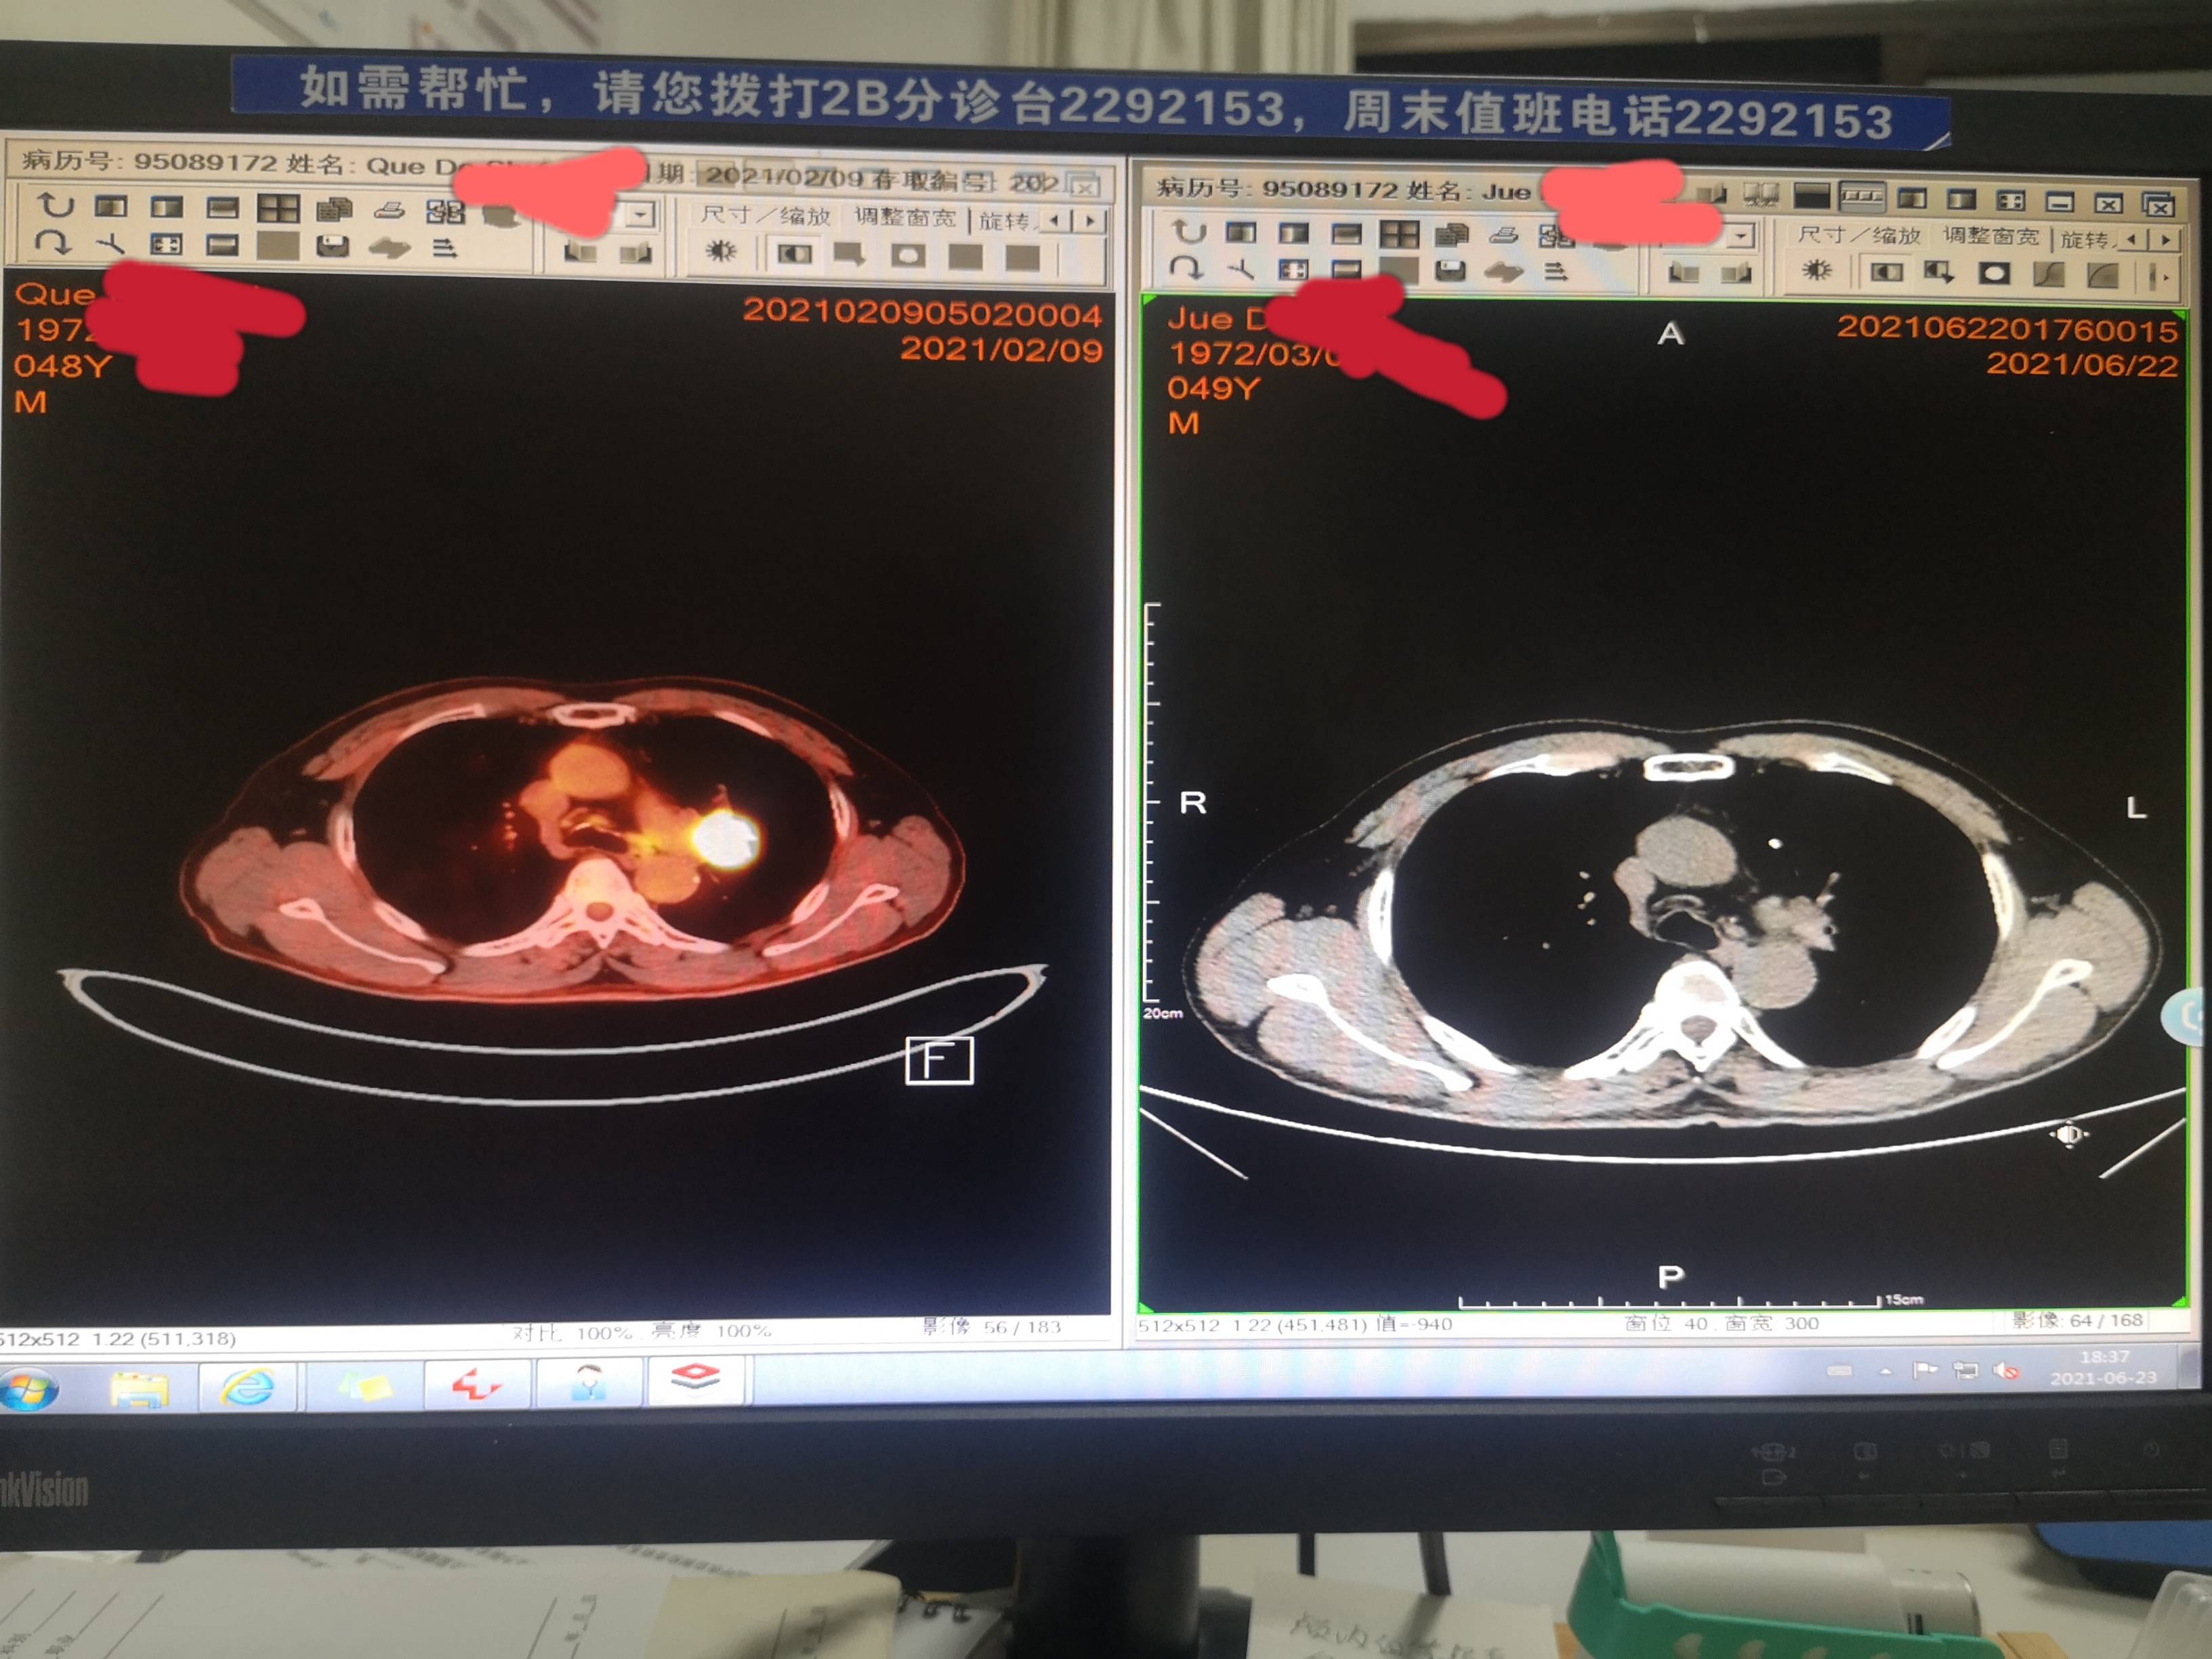

患者拿不定主意,还是先用白紫加铂做了第一周期术前新辅助化疗,因为比较担心,一周期后,做第二次化疗前就提前复查了一次CT,效果似乎不理想

复查效果不错

因为出现心肌酶略增高,三化效果不错,病灶仅剩"少许软组织影"了,故决定抓紧手术。

大家可以注意一下这里,原发灶变成少许软组织影,提示明显变小了,但为什么淋巴结增多,增大呢?

免疫治疗效果很好,淋巴系统激活活跃的话,淋巴结也增大,谓之假进展。